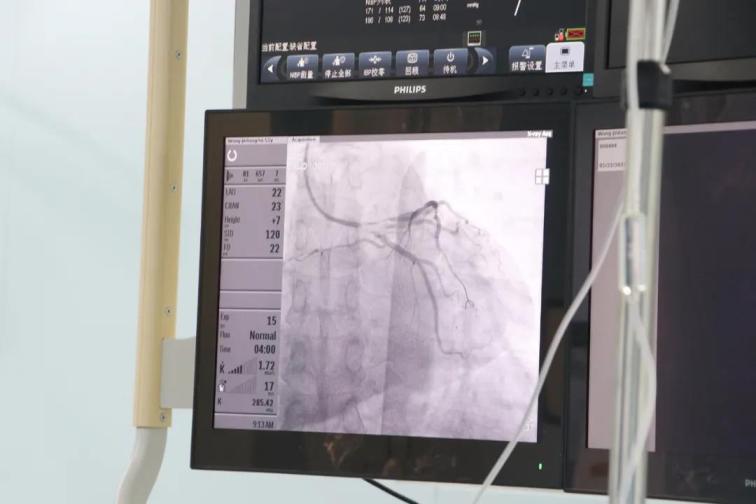

患者王某,男性,52歲,因胸悶半年,加重伴呼吸困難6天于5月8日入院,否認(rèn)高血壓和糖尿病史,外院256排CT提示:左前降支近段局限性中度狹窄,不能完全排除重度可能。入院后行心臟冠狀動脈造影檢查,結(jié)果提示前降支近段狹窄90%,中段狹窄70%,合并心肌橋,遠段狹窄80%,患者及家屬不接受植入支架,在給予前降支近段充分預(yù)處理后,使用藥物涂層球囊送至病變部位,緩慢加壓,持續(xù)擴張45秒,術(shù)后患者癥狀消失,并于5月27日痊愈出院。